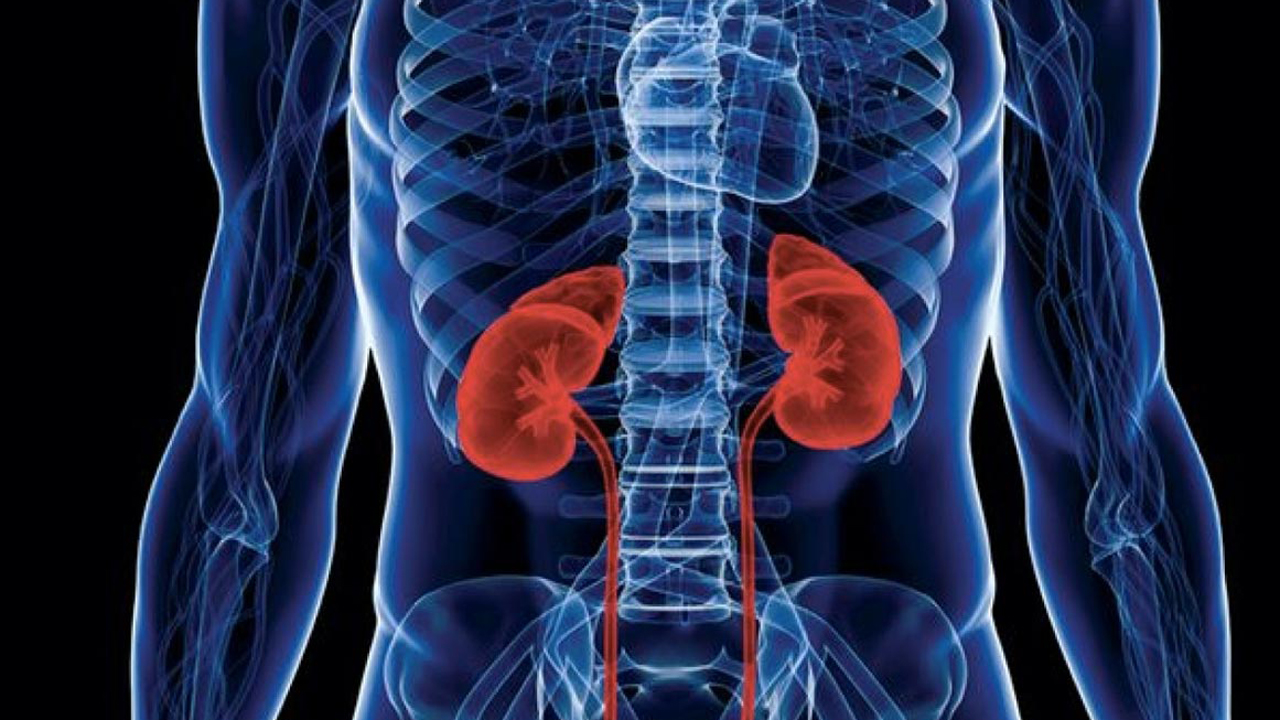

Constipation Drug May Treat Chronic Kidney Disease

A team of scientists led by Professor Takaaki Abe at the Tohoku University Graduate School of Medicine has found that…